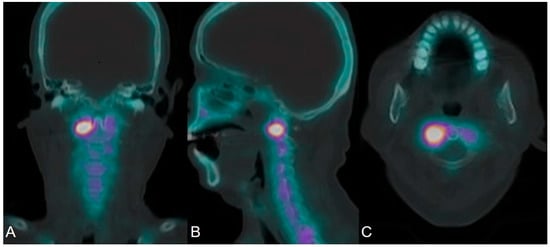

2.4. SPECT/CT